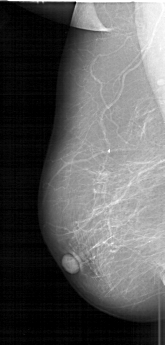

D_4184_1.LEFT_MLO

FILE: D_4184_1.LEFT_CC.OVERLAY

TOTAL_ABNORMALITIES 1

ABNORMALITY 1

LESION_TYPE MASS SHAPE IRREGULAR MARGINS ILL_DEFINED

ASSESSMENT 3

SUBTLETY 5

PATHOLOGY MALIGNANT

TOTAL_OUTLINES 1

BOUNDARY